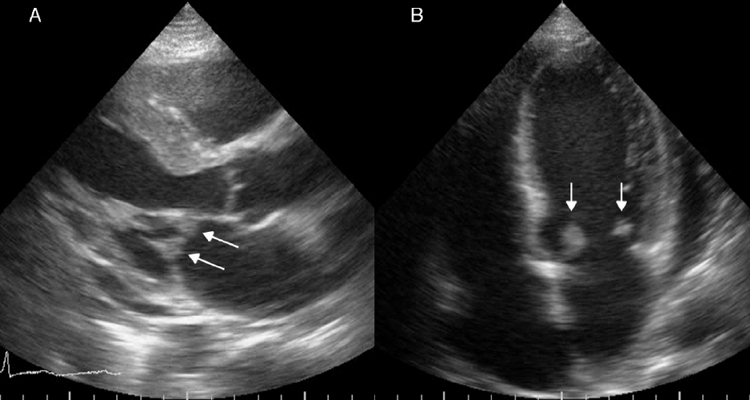

Paciente mujer de 28 años de edad, quien presentó 3 semanas antes de su ingreso, disnea a moderados esfuerzos que progresó a ortopnea. Una semana antes de su ingreso presentó epigastralgia, la cual no se calmó a pesar de diversos tratamientos indicados en centros de salud de su localidad, por lo cual fue trasladada al Servicio de Emergencias del Hospital Universitario de Los Andes. Tiene como antecedentes LES y SAF diagnosticado a los 15 años de edad, sin tratamiento en el momento de la evaluación, por abandono voluntario de la paciente. Presentaba una herida traumática en la pierna izquierda, la cual ameritó injerto de piel en el año 2005 y que, al momento de su ingreso, se encontró sobreinfectada. El servicio tratante solicitó valoración por cardiología, y se realizó ecocardiograma transtorácico (Fig. 1), en el cual se observó engrosamiento de las porciones distales de ambas valvas de la válvula mitral, que generaba imagen de bordes irregulares y condicionaba a insuficiencia leve. Se solicitó hemocultivo, el cual resultó negativo hasta 7 días después de la incubación, y se realizó ecocardiograma transesofágico (Fig. 2), en el cual se observaron imágenes ecogénicas, fijas, de bordes irregulares, adosadas a la superficie auricular de la valva anterior y posterior de la válvula mitral, de 14 × 9 mm y 8 × 5 mm respectivamente. Se solicitó un nuevo hemocultivo, el cual resultó nuevamente negativo. Además de ello la proteína C reactiva y la velocidad de sedimentación globular se encontraban dentro de límites normales, por lo cual no se inició antibioticoterapia. La paciente fue valorada por el servicio de reumatología, quienes determinaron que se encontraba con actividad lúpica e indicaron tratamiento inmunosupresor. Ante todos estos hallazgos clínicos y paraclínicos determinamos que las vegetaciones observadas en la paciente no eran debido a infección bacteriana, sino que concordaban con el diagnóstico de ELS.

Figura 1 Ecocardiograma transtorácico. A. Vista en eje paraesternal largo. B. Vista de 4 cámaras. En ambas vistas se observa imagen de bordes irregulares, que produce engrosamiento de ambas valvas de la válvula mitral en sus porciones distales (flechas).

En el ecocardiograma se pueden observar masas valvulares o vegetaciones, y engrosamiento valvular. Las masas pueden variar de forma y tamaño, generalmente más de 2 mm de diámetro, con bordes que usualmente son irregulares, adheridas firmemente a la superficie valvular auricular o ventricular, sin exhibir movimientos independientes. Las válvulas que se afectan con mayor frecuencia son las del lado izquierdo. Cuando la válvula mitral se encuentra afectada, las vegetaciones se pueden extender al aparato subvalvular y al endocardio adyacente a la valva6. En este caso las masas sobrepasaban los 5 mm, y se encontraban sésiles en la superficie auricular de la válvula mitral, sin extenderse al aparato subvalvular, y como se vio en el ecocardiograma transesofágico había insuficiencia mitral leve.